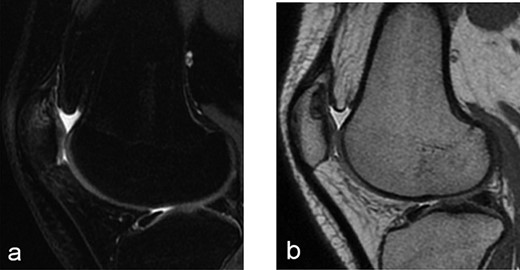

A 14-year-old female dancer presented with increasing right knee pain and functional disability without any trauma. Her pain was retropatellar pain that often radiated medially or laterally from the patella, exacerbated by climbing stairs, running and squatting. She was unable to perform any sports activities. Examination revealed peripatellar tenderness and crepitus, full range of motion and the knee was stable. Radiological examination included both MRI and computed tomography of the knee were performed at the beginning. MRI showed osteochondritis dissecans at the area at the superolateral facet of the patella in the deep subchondral area as shown in Fig. 1. This was appropriately treated conservatively with 6 months of reduced load and protected weight bearing without relief of symptoms. She quit sport activity for 2 years and then another MRI was performed Fig. 2. After 2 years we opted for adipose-derived mesenchymal stromal cells (AD-MSCs) intra-articular therapy according to the procedure described by Tremolada et al. [9]. The patient’s parents were given written information regarding the use of AD-MSCs therapy, including relative risks of this therapy and also relevant treatment alternatives that could otherwise be explored. Postoperative radiological evaluation was performed at 6 months and 12 months after AD-MSCs procedure as shown in Figs. 3 and 4. Postoperative clinical evaluation was performed using IDKC, Lysholm and Tegner scores (Table 1). After surgery, patients began a McConnell program of lateral retinacular stretching, patellar taping and vastus medialis obliquus muscle exercises. The patient was encouraged to swim and cycle to reduce impact loading. Using AD-MSC, she reported a complete relief of pain after 1 year from the procedure. Routine MRI follow-up 2 years later showed evidence of appreciable improvement in cartilage volume and osteochondral architecture at the site of injury. Early MRI T2 mapping at 6 months indicated that the area of cartilage regeneration exhibited high water content suggestive of immature cartilage or fibrocartilage morphology. Later T2 mapping at 18 months after the procedure, indicated progressive maturation of cartilage from deep to superficial layers with more hyaline like cartilage morphology. Limitations of the study are lack of arthroscopic intra-articular visualization and classification of the patella lesion.

Radiographs after 2 years at 16 years old (a) sagital T2-weighted MRI sequences (b) sagital T1-weighted MRI sequences showed the area was still the same at the superolateral facet of the patella in the deep subchondral area.